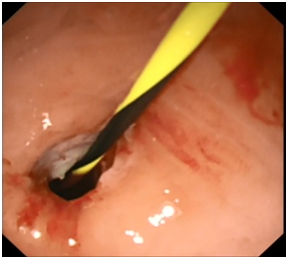

Upon presentation to our hospital, he was complaining of intermittent abdominal pain, post prandial abdominal fullness, however he was not ill and abdominal examination showed distended abdomen with fullness of the left upper quadrant and scars of previous drain insertion. His investigations showed WBC 11.86, Hb 12.8 g/dl, Amylase 123, and Lipase 818. CT Abdomen showed a significant increase in the size of the pancreatic pseudocyst (8x8x12cm). Consent was obtained from his parents for EUS guided cystogastrostomy. Prophylactic antibiotic using Ciprofluxacin was given before and after the procedure for three days. The Olympus EVIS LUCERA Ultrasound Gastrovideoscope GF-UCT 260, 14.6 mm distal tip was introduced easily through the esophagus to the stomach. This showed a large homogenous cyst measuring 8X9 cm, with a clear wall that was adherent to the gastric wall with no intervening blood vessels. This was punctured with 19 G needle and 30 ml of clear aspirate was sent for chemistry and cytology. A guide wire with two loops was formed in the cyst over which a needle knife was used to puncture the gastric wall and create an opening which was dilated to 4 mm. Two pig tail stents 7 Fr 4 cm were placed to drain the cyst. Post drainage, he was doing well, with no signs of complications, and resolution of abdominal pain and distension. He continued to receive antibiotics and was discharge after 2 days of the procedure in a satisfactory condition. His amylase and lipase levels went down to 109 & 631 respectively. The amylase level in the fluid was 7425 u/l, normal CEA level and cytology showed cystic fluid with no malignant cells. Six weeks later, MRI showed complete resolution of the collection and a repeat EUS confirmed resolution of pancreatic pseudocyst. The stent was removed and currently the patient is well and asymptomatic (Figure 4).

Figure 4A & 4B Two pigtail stents in the cyst and plain x-ray showing the stents in the cyst.